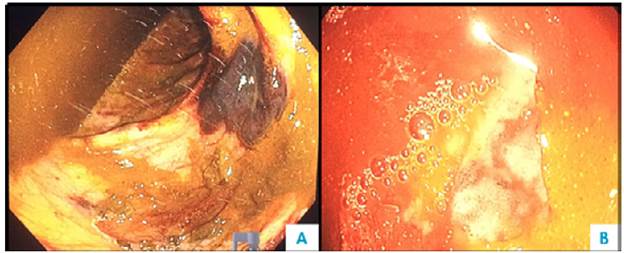

One week after admission, the patient presented acute kidney injury classified as stage 3 KDIGO (discarding prerenal origin, pharmacological toxicity and obstruction) and hypoxemic and hypercapnic respiratory failure, so he was transferred to the intensive care unit (ICU) for invasive mechanical ventilation and initiation of dialysis. Considering the presence of lytic bone lesions and hyperazoemia with nephrotic-range proteinuria by Bence Jones protein filtration, bone marrow aspiration and biopsy were performed, finding 80% of plasma cells (Figure 5). Lambda light chain multiple myeloma ISS III was diagnosed (Table 1). However, a colonoscopy was performed as the patient presented with myopathy, skin lesions, bilateral carpal tunnel, infiltrative cardiomyopathy, hypogonadism, erectile dysfunction and adynamic ileus that were not explained by the myeloma (Figure 6), finding extremely friable mucosa; perineal lesion and renal biopsy were taken to establish the presence of associated systemic amyloidosis.

The patient had gastrointestinal involvement (3.2% frequency) 2; nevertheless, colonoscopy showed ulcerations and friability of the mucosa, classic findings of amyloidosis together with thickening of the intestinal wall, polypoid protuberances, erosions and fine granular appearance of the mucosa. 14 Common symptoms are abdominal pain, esophageal reflux, constipation and nausea. Others include diarrhea, weight loss and early satiety, which may be caused by autonomic neuropathy, bacterial overgrowth or cardiac cachexia. Replacement of intestinal smooth muscle causes dysmotility, pseudo-obstruction and even ischemia secondary to vascular infiltration or ganglion cells depletion. 2 The most involved sites are the duodenum, the rectum and the esophagus. 5,15 Hepatomegaly may be a consequence of congestion or infiltration (by kappa chains, hard and non-pulsatile liver). 3,5 Management is symptomatic with antiemetics, prokinetics and nutritional support 15, but in this case, no medication worked.